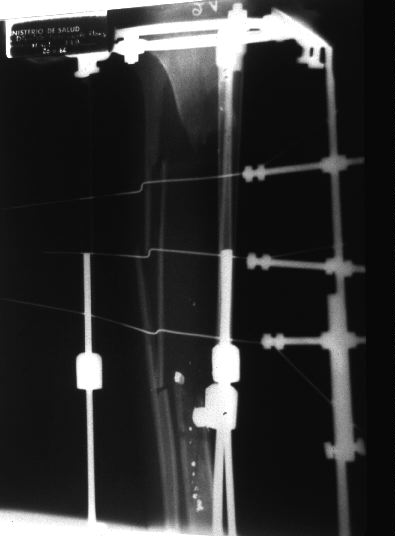

Immediate Post-Op Xray

Due to war-zone conditions and supply shortage, beaded wires were not available. Kinked K Wires were substituted to engage and apply traction to the fibular cortex. Shrapnel from the land mine injury remains in the distal tibial intramedullary canal.